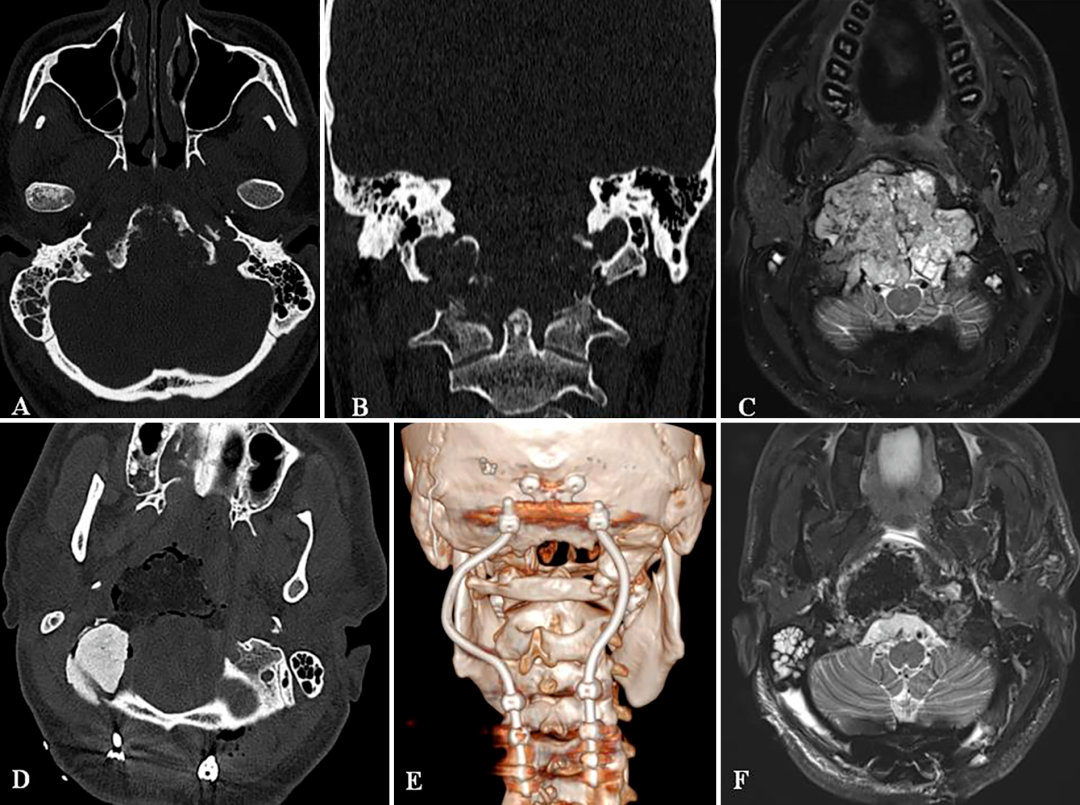

A和B:术前CT扫描显示颅颈交接区脊索瘤,侵犯斜坡-枕髁并呈溶骨性破坏。C:术前MR显示肿瘤巨大延伸,并浸润长入硬膜内的脑实质。D:术后CT显示PMMA枕髁重建稳定良好。E:术后三维CT显示C0-C3-C4-C5枕颈融合稳定,与根钉弯曲有利于PBRT治疗。F:术后MR显示全切肿瘤和脑干延髓占位压迫得到解除。